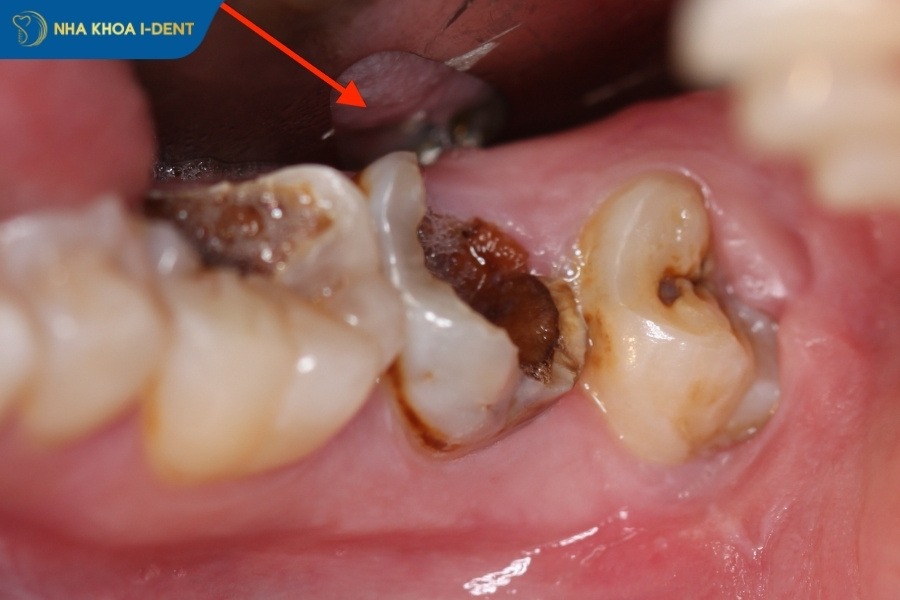

- Răng sâu nặng và cấu trúc răng bị phá hủy: Răng bị sâu vào tủy gây hoại tử và không thể phục hồi, chân răng bị tổn thương nghiêm trọng hoặc bị cụt.

Răng bị sâu nặng, mô răng mất nhiều và gây hoại tử nên nhổ răng.